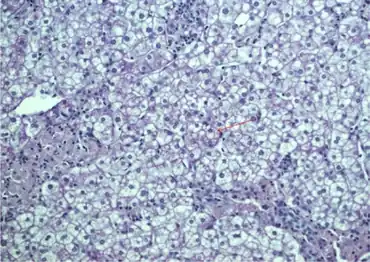

Liver biopsy findings will generally show a bright yellow-orange color, enlarged, lipid-laden hepatocytes and Kupffer cells, microvesicular and macrovesicular steatosis, fibrosis, and cirrhosis.[5] The only definitive tests are genetic, which may be conducted in any number of ways.[7]